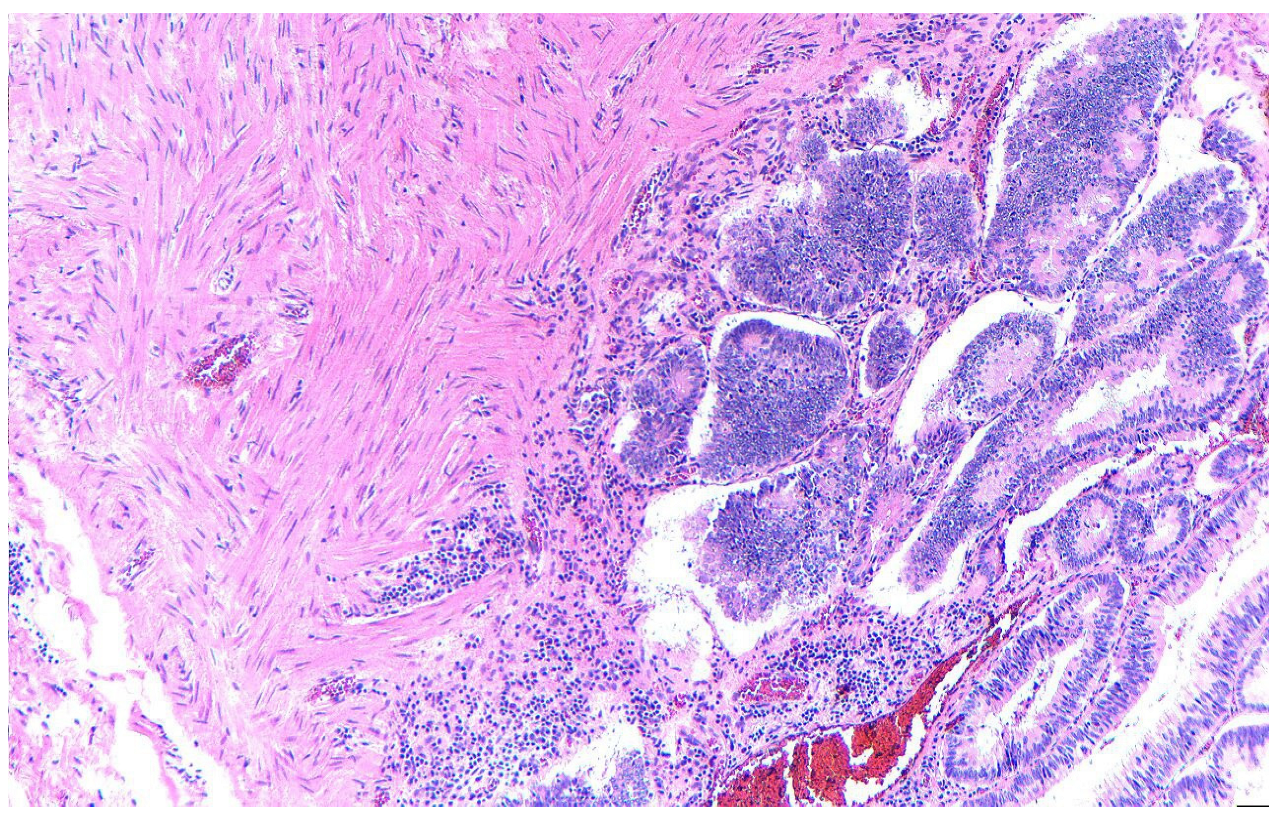

2. Case Presentation